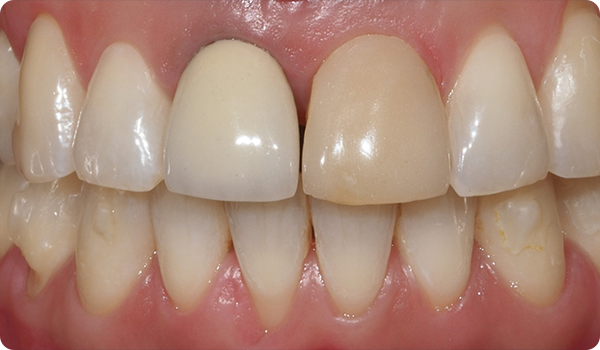

Med små rörelser korrigeras positioner och förbereder den mest lämpliga och konservativa estetiska behandlingen för dina patienter.

Att justera tänder med Right är den perfekta och mest konservativa grunden för framtida blekning eller facettbehandlingar som kommer att föra patientens leende till perfektion.